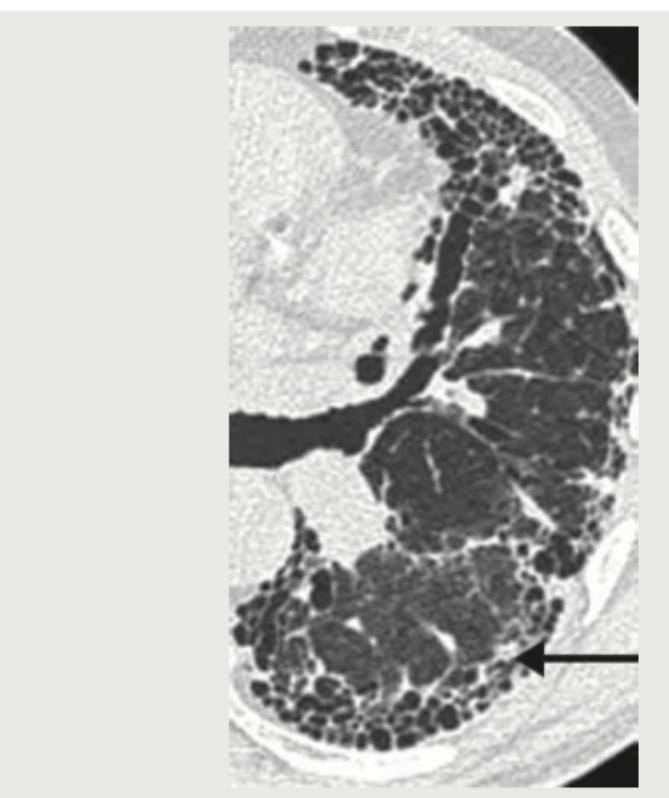

Question 10: The lung parenchyma on CT chest shown below is best described as:

- C. Crazy pavement pattern (Correct Answer)

Explanation: ***Crazy pavement pattern*** - The image distinctly shows a combination of **ground-glass opacities** and superimposed **interlobular septal thickening**, which together create the characteristic "crazy paving" appearance. - This pattern is most commonly associated with **pulmonary alveolar proteinosis**, but can also be seen in conditions like ARDS, PCP pneumonia, and lipoid pneumonia. *Honey comb pattern* - This pattern involves the presence of multiple, clustered, thick-walled **cysts** of varying sizes, typically subpleural, which are a sign of **end-stage lung fibrosis**. - While there are cystic changes in the image, the predominant finding includes ground-glass opacities and septal thickening rather than pure end-stage fibrotic changes. *Signet ring pattern* - A signet ring pattern is classically seen in **bronchiectasis**, where a dilated bronchus is paired with its accompanying smaller pulmonary artery, resembling a signet ring. - The image does not show clearly dilated bronchi adjacent to pulmonary arteries; instead, it displays diffuse parenchymal changes. *Mosaic pattern* - The mosaic pattern refers to areas of differing lung attenuation, often due to **air trapping** (causing dark areas) or areas of **perfusion abnormalities** (creating lighter areas), common in conditions like small airway disease or chronic thromboembolic disease. - While there is some heterogeneity, the specific combination of ground-glass and septal thickening is more accurately described as crazy paving.